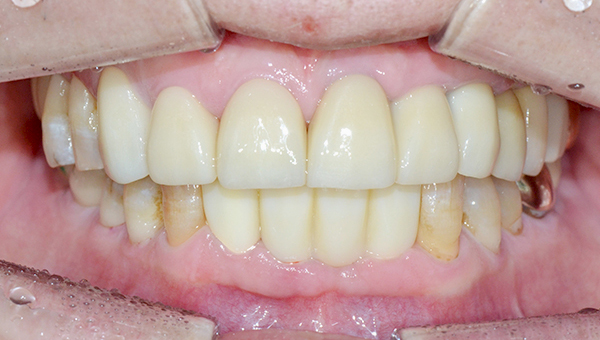

치료사례임플란트

강*란 임플란트 시술 사례

전체 임플란트

2025.02.07

치료 전

2025.08.19

치료 후